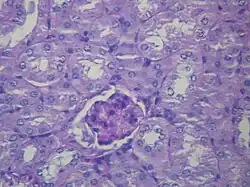

Histologický preparát zdravé ledviny s jedním glomerulem | |